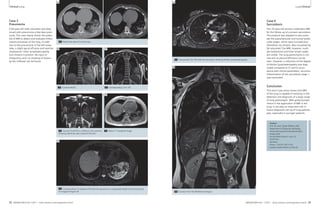

Case 3

Pneumonia

A 66-year-old male volunteer was diag-nosed

with pneumonia a few days previ-ously.

This case clearly shows the poten-tial

of MRI to detect and evaluate inflam-matory

processes of the lung. In addi-tion

to the pneumonia of the left lower

lobe, a slight apical effusion and reactive

mediastinal / hiliar lymphadenopathy

(not shown) is present. No signs of

malignancy and / or masking of lesions

by the infiltrate can be found.

3A Native low-dose CT of the lung.

3B 3C

3B Coronal HASTE. 3C Corresponding T2w TSE.

3D

3D Coronal TrueFISP at a different slice position

showing additional apical pleural effusion.

3E

3E Native T1-weighted image.

3F

Case 4

Sarcoidosis

This 25-year-old woman underwent MRI

for the follow-up of a proven sarcoidosis.

The protocol was adapted to also evalu-ate

the supraclavicular and nuchal lymph

node stages, which were unsuspicious

(therefore not shown). Best visualized by

fat-saturated T2w MRI, however, multi-ple

mediastinal and hiliar lymph nodes

are visible. The lung parenchyma is nor-mal

and no pleural effusions can be

seen. However, a reduction of the degree

of bihiliar lymphadenopathy was diag-nosed

compared to CT and in accor-dance

with clinical parameters, recurrent

inflammation of the sarcoidosis stage 1

was concluded.

Conclusion

4A Transversal T2w TSE with fat saturation showing bihiliar lymphadenopathy.

4B Coronal T2w TSE (BLADE technique).

3F Corresponding T2-weighted TSE with fat saturation at comparable height of the lung to the

CT images in figure 3A.